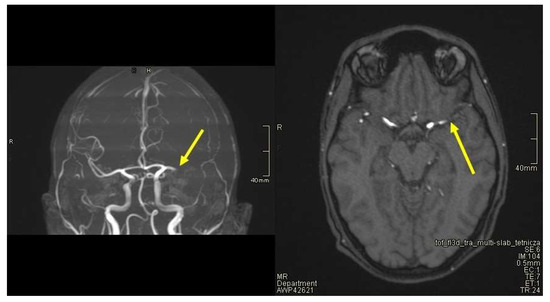

2. Case Presentation